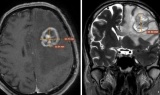

BSCKI. Trần Văn Thụ - Người “giải mã” những ẩn số dưới lớp phim đen trắng